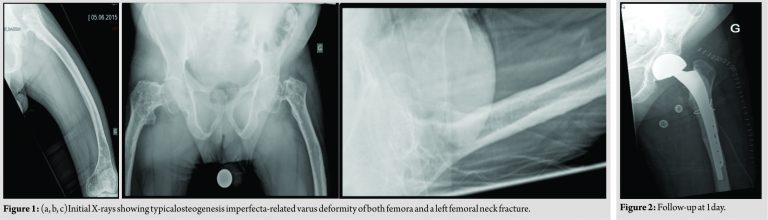

A 52-year-old patient with OI Type III did an unexpected move while sitting in his wheelchair and suddenly suffered from severe pain of his left hip. During clinical examination, typical OI-related varus deformity of both femora was found. His left groin was tender on palpation, and hip joint motion was restricted. There was no sign of cutaneous lesion and no neurovascular compromise. Previous to this incident, the patient was able to walk a few meters with the help of a walking device and was using a wheelchair for the rest of the time. Besides OI, he was not known for any other medical conditions. He reported multiple fractures during his childhood. He never complained of left hip joint pain previous to this accident. X-rays showed a displaced femoral neck fracture with varus deformity Type III according to the Pauwels’ classification. The varus angulation of the left femur was 30°,and posterior angulation was 20°.

Apart from the fracture, X-rays showed thin cortices and heterogeneous bone density (Fig. 1a, b, c). We perform a hemiarthroplasty of the left hip with a bipolar cup and a straight, cemented stem (BIBOP cup size 44, stem ARCAD L, size B, both Symbios Orthopédie, Yverdon-les-Bains, Switzerland), combined with a valgus and shortening osteotomy of the left proximal femoral shaft (Fig.2, 3a and b). The patient started physical therapy with active assisted mobilization of his left hip and knee and strengthening of his gluteal and quadriceps muscles on day 1. He was also allowed full weight bearing and was rapidly able to switch from bed to his wheelchair and back by himself. He was discharged from hospital on day 9. At 2 years follow-up, the patient reported no pain, and his ability to mobilize himself was back to the pretrauma state, while the site of osteotomy showed signs of bony healing on X-ray (Fig. 4a and b).